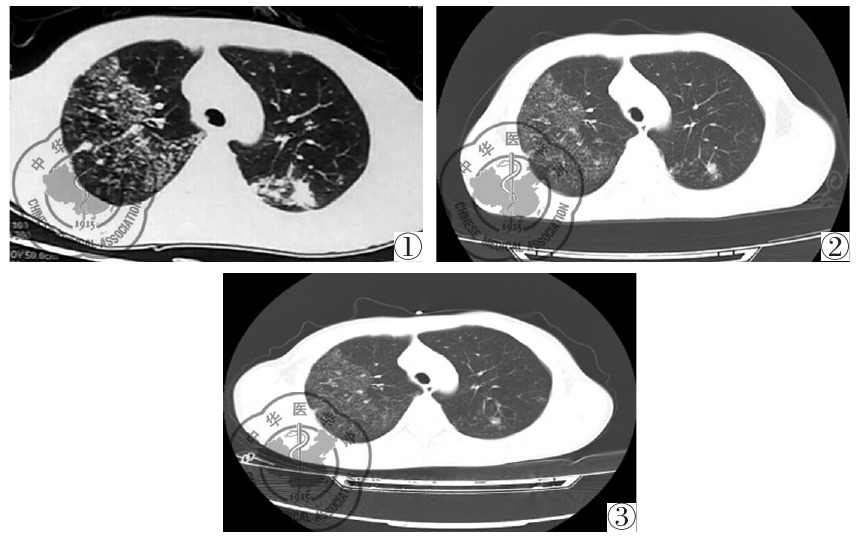

图3 患者经抗结核治疗2月后胸部CT影像学表现